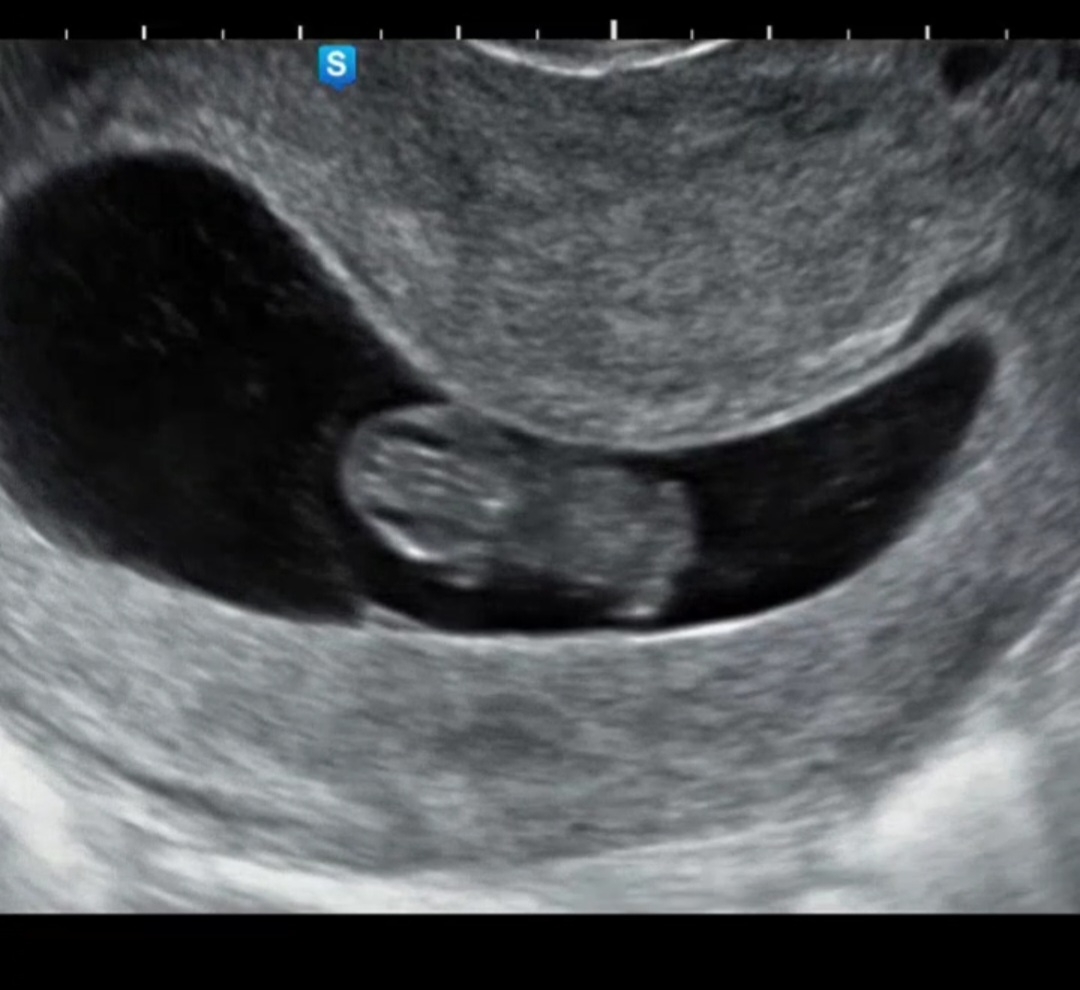

9주1일 하리보♡

동영상 못올리는게 아쉽네요ㅜ 열심히 꼬물꿈틀 움직이고, 심장은 180 넘게 두두두두 뛰더라구요ㅎㅎ 3주 후 첫 기형검사 있는데 떨리네요ㅜ 설 지나고 또 보러갈께 레몬아♡